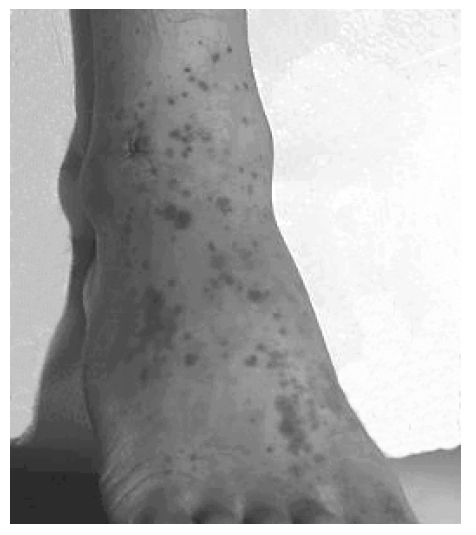

A 20-year-old woman was admitted to hospital because of arthralgia on both ankles and palpable purpura on both legs for 5 days. Physical examination showed multiple purpura on legs and buttock and swelling and tenderness on both elbows and ankles (Figure 1). Laboratory data showed normal blood counts, blood chemistry and urine analysis. C-reactive protein was 3.7 mg/dL and ESR was 21 mm/hr. Tests for antinuclear antibody, rheumatoid factor and antineutrophil cytoplasmic antibody (ANCA) were negative. Serum concentrations of immunoglobulin (Ig)G, IgA, IgM, C3 and C4 were normal. A biopsy specimen of skin lesions showed leukocytoclastic vasculitis and immunofluorescent study revealed IgA depositions on vessels (Figure 2).